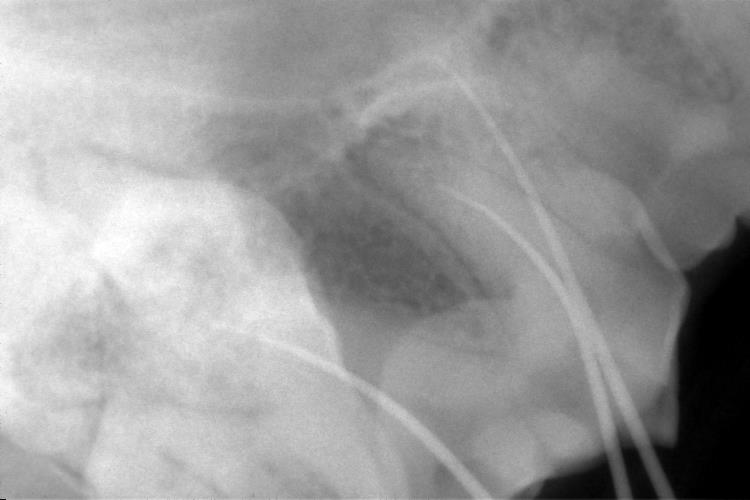

この時、ファイルが根尖まで達しているかレントゲン検査で確認します。

レントゲンにて、根管の長さと太さを確認します。

根管の充填が適切に出来ているか、レントゲンにて確認します。

レントゲン検査を行い、適切に充填できているか確認を行いました。